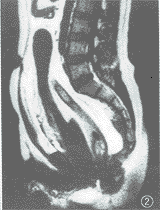

腹部MRI检查:膀胱位于中下腹部,上界抵达L3水平,下缘距耻骨联合上缘5 cm。其外观在矢状位及横断位呈扁囊状,冠状位呈倒泪滴状,侧面下部受压使其变形。膀胱内尿液呈均匀长T1长T2信号。膀胱周围包绕脂肪组织,呈短T1长T2信号,厚度达2~6 cm不等,其顶部脂肪层较薄。盆腔内也充填大量脂肪组织,前列腺位置上移。在脂肪抑制序列图像,腹盆腔脂肪组织信号被抑制,表现为大片低信号区(图2~5)。

图2 腹部MR正中矢状位T1WI显示膀胱呈扁囊状,因脂肪积压,前后径变窄